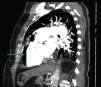

A 84-year-old woman was referred to our emergency department from another hospital with acute dyspnea at rest and hypoxemia. On admission a peripheral venous catheter had been inserted for fluid replacement and she had undergone computed tomography pulmonary angiography (CTPA) for suspected pulmonary embolism. Soon after the exam the patient became confused and drowsy and her respiratory failure worsened significantly without hemodynamic instability. CTPA confirmed the presence of bilateral central and peripheral thrombus and a large amount of air in the brachiocephalic veins, pulmonary artery (Figure 1) and right ventricle (Figures 2 and 3). She was considered to have VAE unrelated to the administration of contrast, given a topogram image that suggested the presence of air in the right ventricle before contrast injection (Figure 4). It was therefore assumed that the VAE resulted from the placement or manipulation of the peripheral venous catheter previously inserted in another institution. The patient was immediately given normal saline, a Hudson mask was applied and she was placed in left lateral decubitus position (Durant's maneuver) and in the Trendelenburg position, to keep the right ventricular outflow tract lower than the right ventricular cavity causing the air to migrate upwards, minimizing the likelihood of embolism. Her clinical status improved rapidly and she recovered without sequelae. Bedside transthoracic echocardiography showed no acute ventricular dilation or dysfunction, and the patient was transferred to another hospital for hyperbaric oxygen therapy.